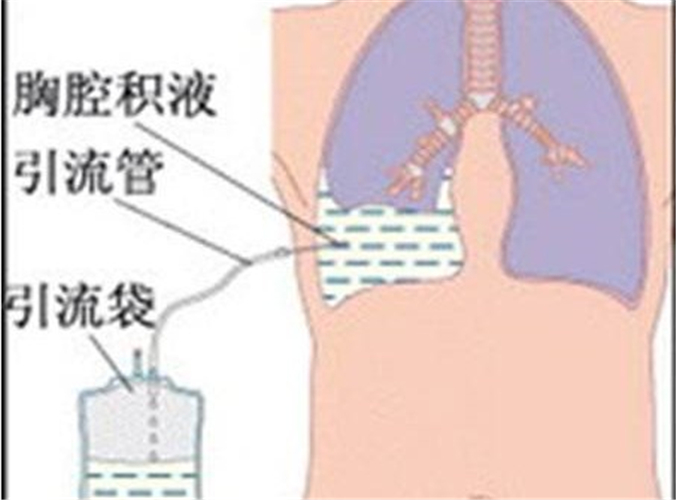

結核性胸膜炎引流

結核性胸膜炎胸腔的積液

結核性胸膜炎胸腔積液的

結核性胸膜炎胸腔積液

A:胸腔積液結核性胸膜炎,主要是由於結核桿菌的感染引起,造成胸膜出現炎症反應,胸膜滲出而形成胸腔積液,積液表現為草綠色、澄清的液體,或者合併胸悶、胸痛、低熱、乏力、消瘦等相關的症狀。如果診斷為結核性胸膜炎,患者胸腔積液量較多,需要進行胸腔穿刺……